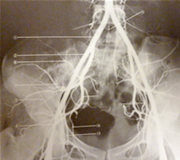

骨盤は歪みません!35年来 骨盤、股関節撮影で骨盤が歪んでいる患者さんは少ないです。

股関節可動性減少の人は先天的股関節脱臼などのX線撮影が必要不可欠です。

症状によって提携医療機関で私自身が撮影し分析を行いますので御安心下さい。

放射線科でX線撮影して気付いた事は右脚が痛い患者さんは反対側の股関節が悪く歪んでいる事です。

右脚を治療するより左の股関節の治療をしなければならないという事です。